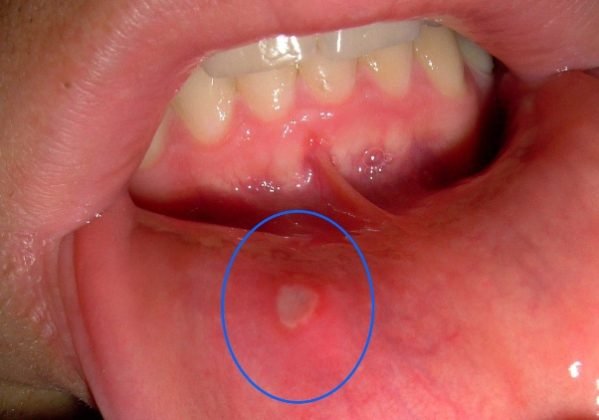

- Ove ranice se najčešće pojavljuju kao bijele ili žućkaste promjene okružene crvenim rubom, a mogu se razviti na različitim mjestima unutar usta – na unutrašnjosti usana, obrazima, jeziku ili čak pri dnu usne šupljine. Njihova veličina varira, a iako obično prolaze same od sebe u roku od nekoliko dana do dvije sedmice, taj period može biti izuzetno neugodan.

- Pored bola, prisutna je i stalna nelagodnost, naročito prilikom konzumacije hrane i pića. Osoba može razviti čak i strah od jedenja, što dugoročno može uticati na apetit i opšte stanje organizma.Vizuelno, afte su lako prepoznatljive, ali njihov broj i veličina mogu varirati. Neki ljudi imaju samo jednu ranicu, dok se kod drugih javlja više njih odjednom, što dodatno pogoršava stanje.